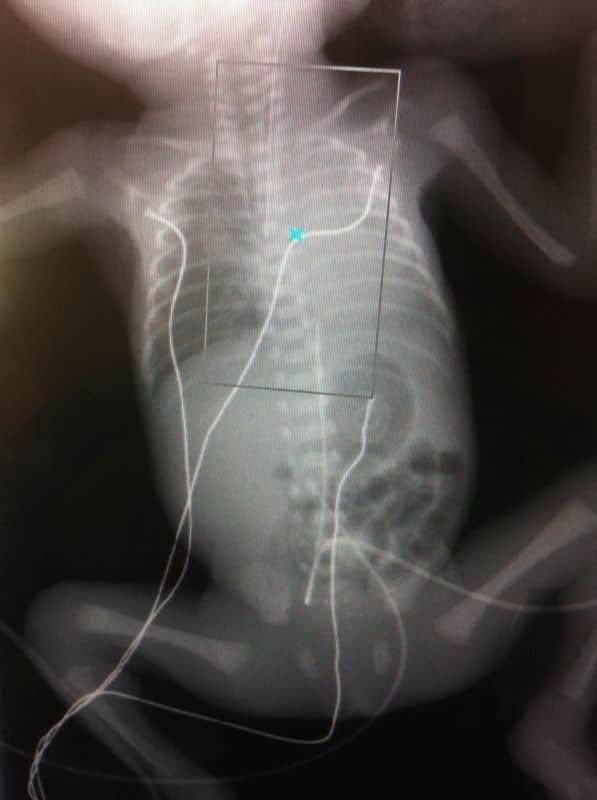

Neonato prematuro de 24 Semanas

Abdomen Simple: